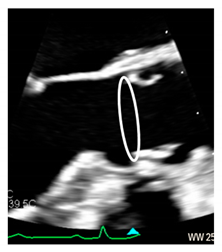

| Ventricular–arterial junction | The term ventricular–arterial junction describes the border between the ventricular myocardium and the fibroelastic structure of the aortic root. Contrary to the right AV junction, where the pulmonary root is entirely supported by the muscular infundibulum, only the left and the right coronary sinuses are partially supported by the myocardium (see text), being the remaining extent of the aortic root supported by fibrous tissue (MS = membranous septum; see text and references [12,13]). | ![]() |